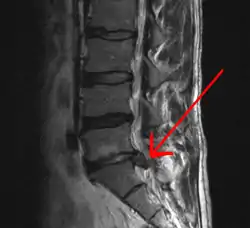

- Magnetic resonance imaging is the gold standard study for confirming a suspected LDH. With a diagnostic accuracy of 97%, it is the most sensitive study to visualize a herniated disc due to its significant ability in soft tissue visualization. MRI also has higher inter-observer reliability than other imaging modalities. It suggests disc herniation when it shows an increased T2-weighted signal at the posterior 10% of the disc. Degenerative disc diseases have shown a correlation with Modic type 1 changes. When evaluating for postoperative lumbar radiculopathies, the recommendation is that the MRI is performed with contrast unless otherwise contraindicated. MRI is more effective than CT in distinguishing inflammatory, malignant, or inflammatory etiologies of LDH. It is indicated relatively early in the course of evaluation (<8 weeks) when the patient presents with relative indications like significant pain, neurological motor deficits, and cauda equina syndrome. Diffusion tensor imaging is a type of MRI sequence used for detecting microstructural changes in the nerve root. It may be beneficial in understanding the changes that occur after herniated lumbar disc compresses a nerve root, and might help in differentiating the patients that need surgical intervention. In patients with a high suspicion of radiculopathy due to lumbar disc herniation, yet the MRI is equivocal or negative, nerve conduction studies are indicated.[44] T2-weighted images allow for clear visualization of protruded disc material in the spinal canal.

A rather severe herniation of the L4–L5 disc